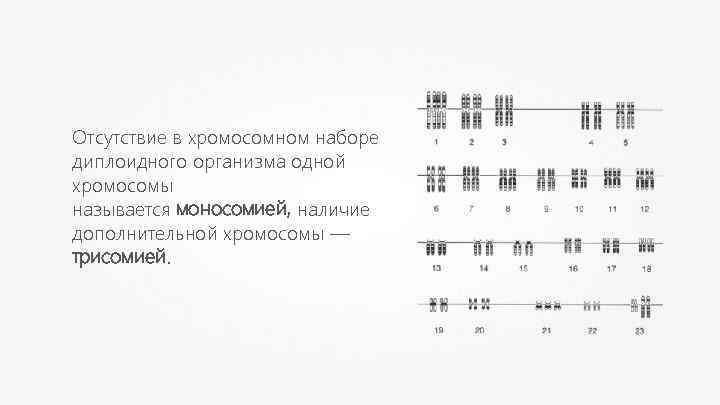

Анеуплоидия — изменение числа хромосом в геноме организма, не кратное гаплоидному набору.

Отсутствие в хромосомном наборе диплоидного организма одной хромосомы называется моносомией, наличие дополнительной хромосомы — трисомией.

Анеуплоидия возникает в результате нарушения расхождения хромосом в митозе или мейозе. Анеуплоидия вызывает у человека наследственные патологии.

Анеуплоидия Синдром Дауна Синдром Шерешевского-Тёрнера